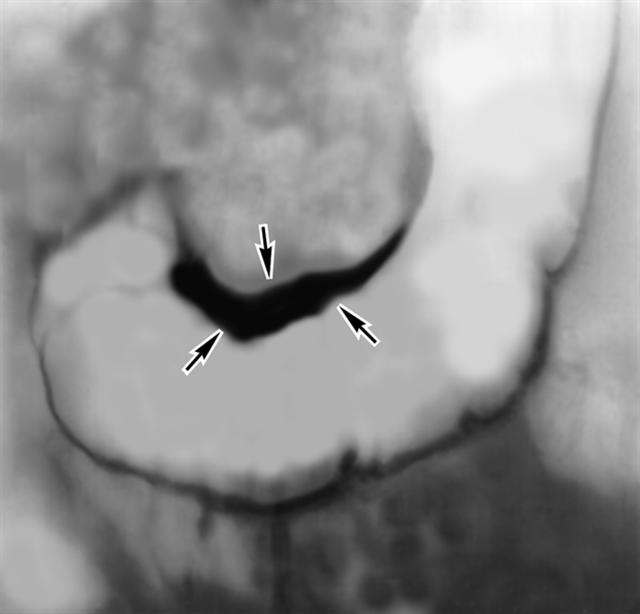

Рис. б). Париетограмма желудка при инфильтративном раке малой кривизны: толщина пораженного участка (указан стрелками) достигает 10—15 мм и более.